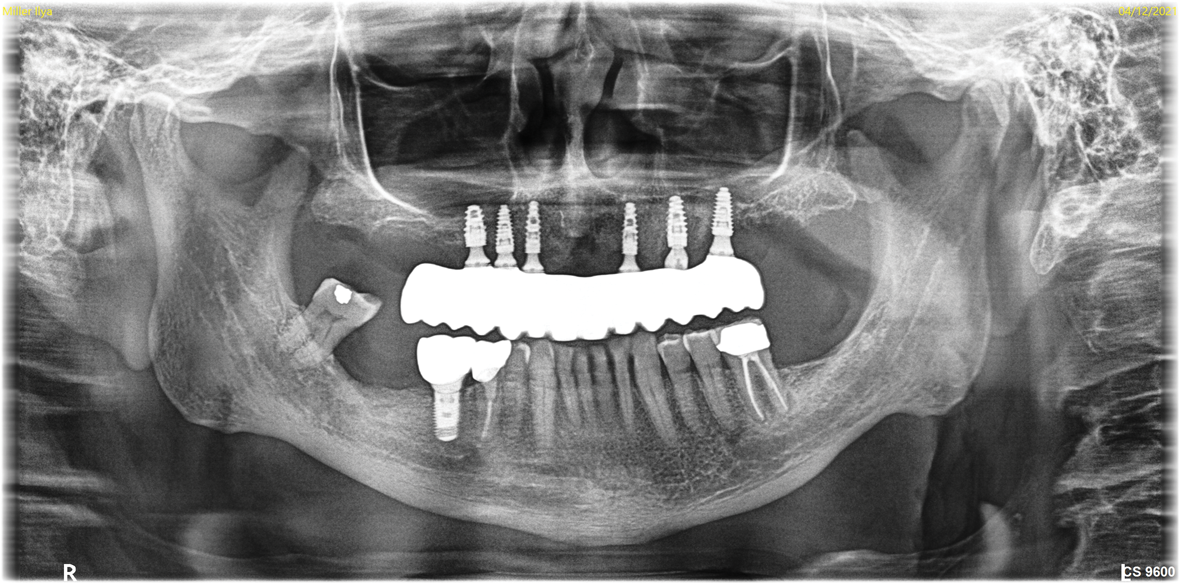

Fig 12. CBCT of final implant placement with

cross-section of maxillary left side sinus elevation.

Figure 12

Fig 16. Final panoramic x-ray.

Figure 16